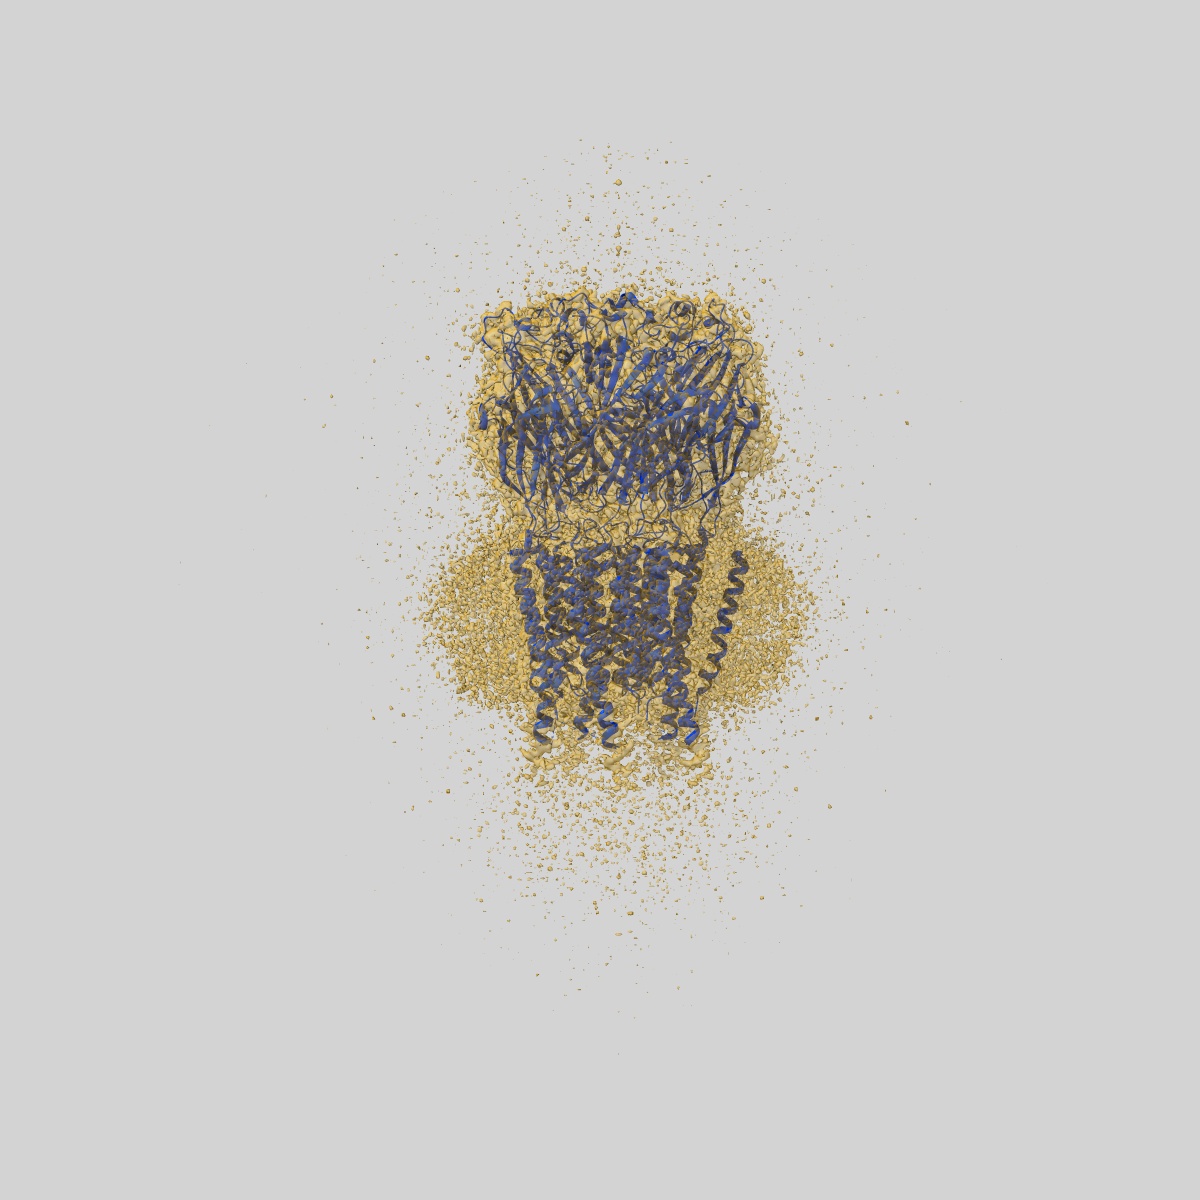

CryoEM structure of human rho1 GABAA receptor in complex with (R)-GABOB in the primed state

Sample Organism: Homo sapiens

Sample: human rho1 GABAA receptor

Fitted models: 9frh

Cryo-EM structures of rho 1 GABA A receptors with antagonist and agonist drugs.

Fan C , Cowgill J , Howard RJ , Lindahl E

(2025) Nat Commun , 16 , 7077 - 7077